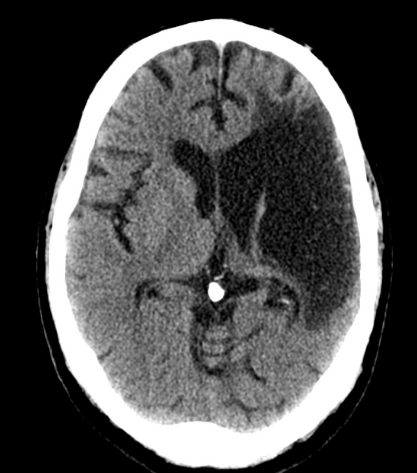

Q

A

EVC hemorrágico subagudo (36 hrs)